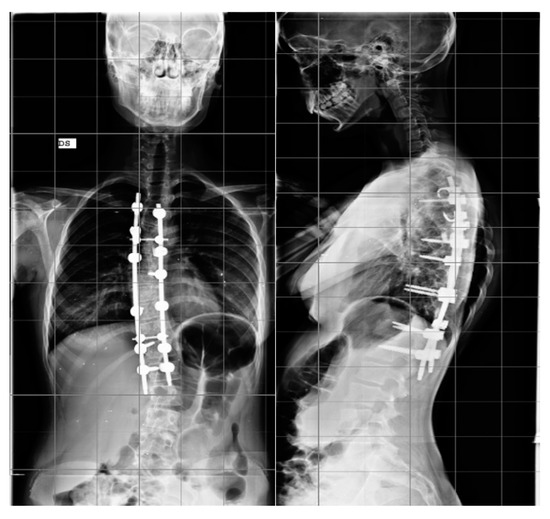

Step 4. Correction maneuvers: A first step of correction was performed by a previously countered rod into the reduction tabs, using the setscrews to reach the screw head. This way, a translation of the spine to the rod was obtained. After the rod was engaged in all anchors, the rod rotation instruments were attached to the rod and the surgeon, together with the assistant, performed a global de-rotation of approximately 90° in the direction of the concave side (Figure 3).

Figure 3.

Intraoperative view of AIS correction maneuvers.

To obtain additional correction, especially when an axial correction was needed, a segmental de-rotation could be performed by inserting the second contoured rod on the convex side and then anchoring the screw set on the screw head to perform bilateral de-rotation. At the end of the correction maneuvers, the insides of the rods were examined and connected using two transverse connectors.